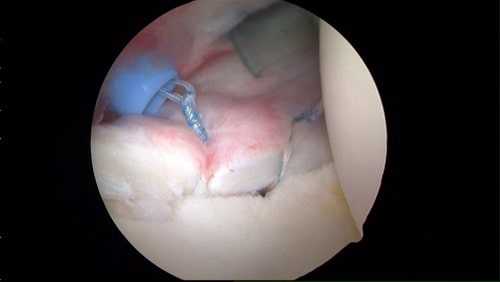

Во время артроскопии, визуализируется место повреждения, в кости в проекции отрыва, сверлятся каналы, а в них вводятся специальные якорные фиксаторы (анкеры), к которым сверхпрочными нитями производится фиксация суставной губы. Для операции может потребоваться несколько якорных фиксаторов.

Якорный фиксаторы (анкеры) могут быть изготовлены из металла или специального рассасывающегося материала. Через некоторое время суставная губа прирастает к кости. Якорные фиксаторы удалять в дальнейшем не требуется.